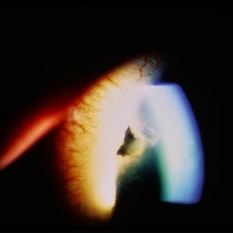

Anterior segment image with subconj heme.

Condition/keywords: trauma